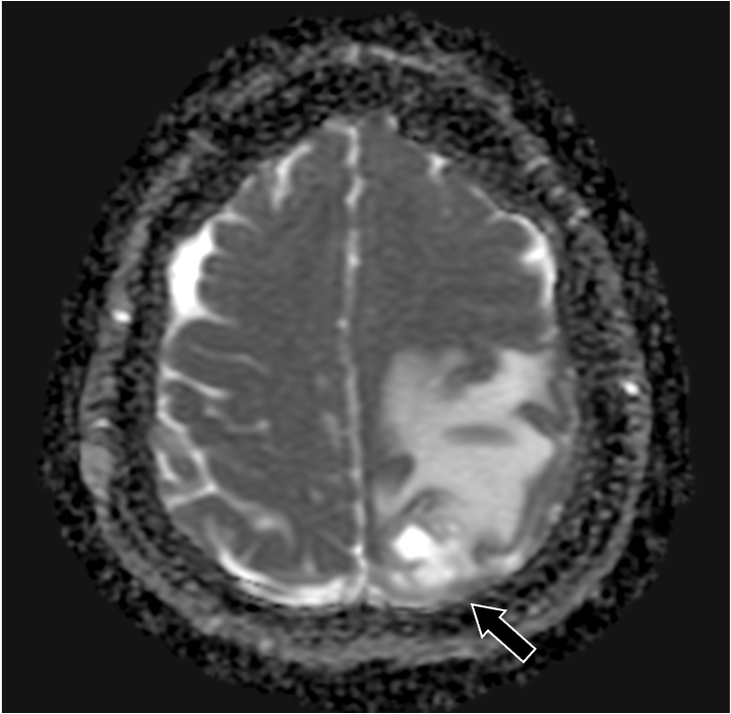

202X年より右手指知覚障害、頭痛を自覚。数日後から頻回嘔吐や右下肢運動障害があり、頭部造影MRIにて精査。既往に転移性肺腫瘤の治療歴あり。

症例解説

201X年腎細胞癌に対して手術を施行。術後経過で肺転移が出現。外科的切除および化学療法にて縮小を維持していた。202X年神経症状が出現し、頭部造影MRIにて左頭頂葉の孤発性脳転移と診断された。開頭腫瘍摘出術および定位照射を行い、再発なく経過している。

造影MRI検査は単純MRI検査と比較して、追加病変の検出能や診断精度の向上が示されている。造影MRI検査は、非腫瘍性白質疾患(慢性微小血管虚血性疾患など)を転移性腫瘍と鑑別する上でも有用である。脳腫瘍では腫瘍周囲に血管原性浮腫を認める場合があるが、高悪性度の原発性脳腫瘍と比較して、転移性脳腫瘍では腫瘍径に対する血管原性浮腫の面積が広いことが報告されている。単純MRI検査では腫瘍径を過大評価する可能性があり、術前・放射線治療計画等に際して造影MRI検査による適切な評価が求められる。